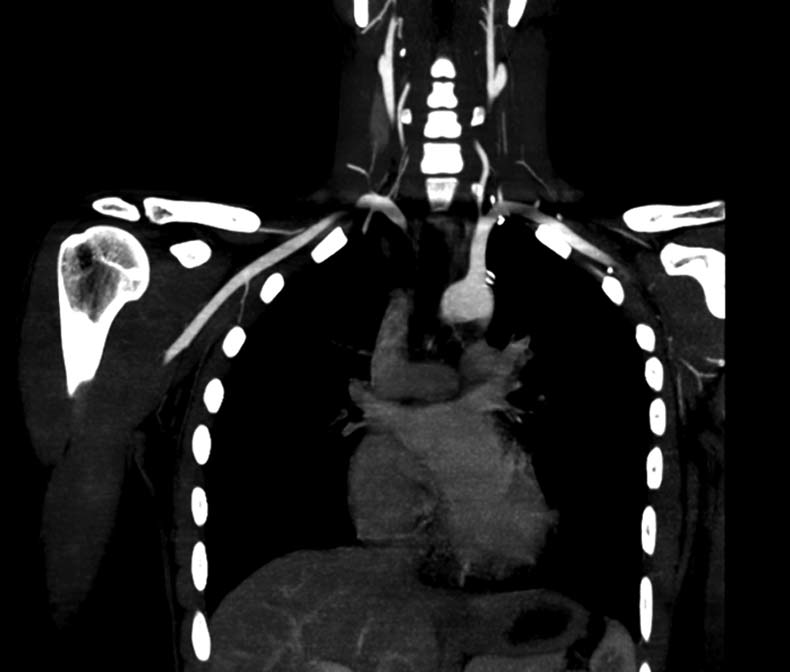

A 27-year-old man was referred for endovascular intervention to the left subclavian artery. There was no history of giddiness or claudication pain in the upper extremities. On examination, the left upper limb pulses were feeble. Blood pressure was 160/ 90 mm Hg in the right upper limb and 110/90 mm Hg in the left upper limb. There was a bruit in the left supraclavicular area. Routine blood investigations, including inflammatory markers, were normal. CT angiography revealed a discrete narrowing of the third part of the left subclavian artery (figure 1). A diagnosis of aorto-arteritis was considered, based on American College of Rheumatology criteria. However, there was no thickening of the vessel wall. The patient was re-evaluated. Wright’s hyperabduction test was performed.1 The signs disappeared with the arm in an adducted position and were reproduced in the abducted position. Repeat CT in the adducted position showed no evidence of subclavian obstruction (figure 2). A diagnosis of dynamically induced arterial thoracic outlet syndrome was made.

Figure 1 CT angiogram showing discrete stenosis in the third part of the left subclavian artery.